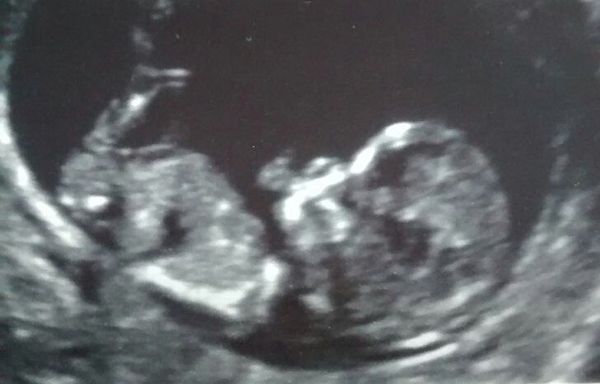

Suziesome1 · 02/02/2016 15:08

Well here's our sproglette :) its amazing seeing/hearing them in the scans isn't it? Date changed by one day so I'm now edd 14 August. Which makes me 12+2 :) I'm very happy, and am actually starting to believe there may be a baby at the end of this! Smile

Here it is!! Baby was asleep for most of the appt, just moved a tiny bit from all the prodding and poking. Heart was beating away though Smile